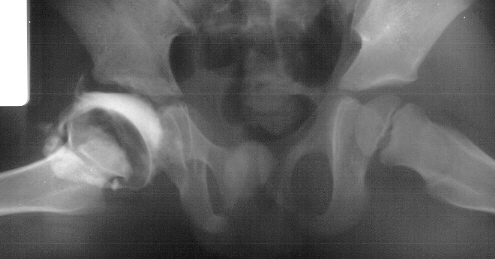

- Post Operative Day 18: R hip Xray: subluxation of R hip, possible metaphyseal

lucency consistent with osteomyelitis. Taken to OR for repeat I & D

of R hip via posterior approach with Penrose drains and hip spica cast

(15cc seropurulent fluid drained). Antibiotics changed to Oxacillin 225mg

IV q4.

Institute. Initial labs: WBC 15,100, ESR 72. R hip Xray: changes in proximal

. metaphysis including lucency and demineralization, hip subluxated. Treated

with oxacillin and Pavlik harness.

- 2 month Office Follow Up: Rt hip Xray: progressive destruction of capital

femoral epiphysis, cystic changes in metaphysis consistent with AVN.